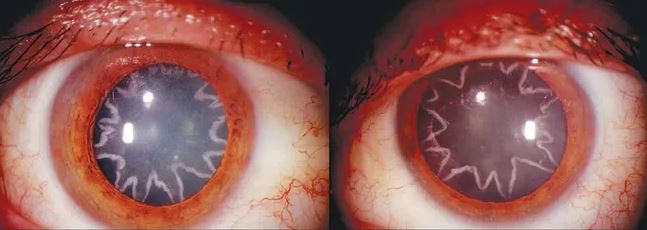

Muž po nehode v práci skončil s „očami v tvare hviezdy“

Tento chlapík posunul videnie hviezd na novú úroveň – po hororovej nehode v práci mu zostali „oči v tvare hviezdy“. 42-ročný muž mal naozaj ťažký deň v práci a skončil so šedým zákalom v tvare hviezdy. Správa o jeho bizarnom stave sa prvýkrát objavila na titulkách v roku 2014, keď bol prípad publikovaný vo vydaní New England Journal of Medicine z 23. januára.

K incidentu došlo v skutočnosti desať rokov predtým – chlapík však o desať rokov neskôr stále trpel problémami so zrakom na oboch očiach. Nemenovaný elektrikár pracoval v Kalifornii, keď ho počas smeny zasiahlo desivých 14 000 voltov. Jeho rameno sa náhodne dostalo do kontaktu so živým drôtom, čo spôsobilo, že vysokonapäťový prúd prerazil jeho telom a skrížil sa s jeho optickým nervom. Skladá sa z miliónov nervových vlákien, ktoré prenášajú impulzy z vašich očí do mozgu a tieto zmyslové informácie sú potom spracované, čo nám umožňuje vidieť. Tých 14 000 voltov ho očividne poriadne prepražilo – najmä na jeho dvoch očných buľvách.

Podľa The New England Journal of Medicine mu na očiach zostalo pár elektrických popálenín v tvare hviezdy. Dr Bobby Korn, docent klinickej oftalmológie na Kalifornskej univerzite, liečil pacienta kvôli tomuto podivnému zdravotnému stavu. Pre NBC povedal: „Optický nerv je podobný akémukoľvek drôtu, ktorý vedie elektrinu. V tomto prípade extrémny prúd a napätie, ktoré prešli týmto dôležitým prírodným drôtom, spôsobili poškodenie samotného zrakového nervu.“

Po štyroch týždňoch od nehody sa muž sťažoval, že má stále problémy so zrakom. Dôkladné vyšetrenie zistilo, že podľa Korna má „nápadný šedý zákal v oboch očiach“ v nezvyčajnom tvare. Šedý zákal nastane, keď sa šošovka oka zakalí, čo spôsobí, že sa váš zrak celkom zahmlí, čo je hlavnou príčinou slepoty. Štyri mesiace po tom, čo bol zasiahnutý elektrickým prúdom, pacient podstúpil operáciu na odstránenie šedého zákalu v prospech novej šošovky, čo pomohlo jeho videnie mierne zlepšiť.

Poškodenie jeho zrakového nervu je však niečo, čo sa nedalo napraviť – to znamená, že jeho zrak bol stále obmedzený. Korn povedal, že pacient stále hlási tieto problémy aj desať rokov po incidente.